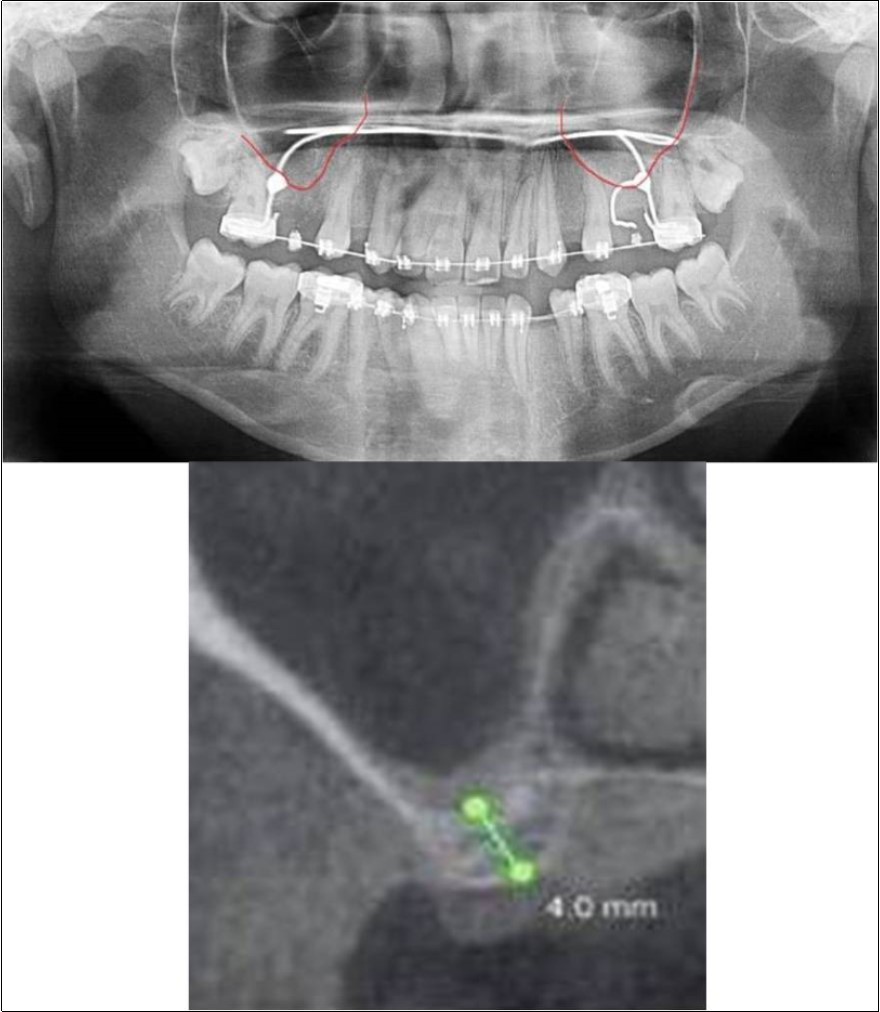

Case Report 4:

A 19 years old young female patient reported to the Department of Oral and Maxillofacial Surgery, D.A.P.M.R.V Dental College and Hospital seeking options for replacement of her missing right and left upper first molars with a fixed prosthesis as she was uncomfortable with the removable partial denture i.r.t 16 and 26. The teeth were extracted 6 months ago because of gross loss of crown structure and poor prognosis for root canal treatment. Patient was also undergoing fixed orthodontic treatment for proclined upper anteriors. Patient did not give history of any existing sinus pathologies. All possible rehabilitative options were explained to the patient and a treatment plan of replacement of missing teeth with implant supported prosthesis using two dental implants was finalized.

Clinical and Radiological Assessment:

1.Partially edentulous maxillary arch with missing 16 and 26;

2.Increased pneumatisation of right and left maxillary sinus;

3.Height of available bone-

16 region: 6.5mm;

26 region: 6.2mm;

4.Transverse thickness of available bone (CBCT evaluation)-

16 region: 8.3mm;

26 region: 10.5mm;

5.Fixed orthodontic appliance;

6.Inter-ridge space adequate to place implant (11mm).

Treatment:

Patient underwent the procedure of indirect sinus elevation using sinus osteotomes in relation to 26 region. Calcium phosphosilicate putty was dispensed as the graft material through the crestal osteotomy site to maintain the elevated sinus membrane followed by placement of 5 x 10mm dental implant under local anaesthesia and strict aseptic protocols. The implant was allowed to osseo-integrate for a period of six months during which the patient was followed-up periodically and was assessed for peri-implantitis, crestal bone loss and mobility. Patient was taken-up for direct sinus elevation via lateral window approach for sinus augmentation i.r.t 16 region. Under aseptic conditions and local anaesthesia, lateral wall of maxilla was exposed after muco-periosteal flap elevation. A window was created of 1cm diameter corresponding to apical aspect of 16. Sinus membrane was identified and elevated using sinus elevators and reamers without perforating the lining. Once the sinus membrane was elevated, phosphosilicate putty was dispensed through the lateral osteotomy site as the graft material to achieve an augmentation of 1cm assessed clinically and confirmed using post-operative OPG. At the end of 6 months, a repeat CBCT scan was advised to evaluate the increase in bone height. (Figure 13a,b, pre-treatment; Figure 14a,b, post-treatment)

Figure 13.(a,b) Pre-treatment OPG and cross section of CBCT showing residual alveolar bone height for Case No.4;